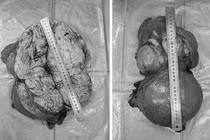

Khối u buồng trứng khổng lồ - Ảnh BVCC

Kết quả siêu âm và chụp Ctscanner ổ bụng có hình ảnh khối dạng nang lớn vùng tiểu khung kích thước 12,8x15cm. Các bác sĩ đã hội chẩn chuyên khoa sản, chẩn đoán u lớn vùng tiểu khung, nghi ngờ u nang buồng trứng trái.

Quan sát trên màn hình nội soi phát hiện khối u dạng nang kích thước khoảng 15cm dính vào tử cung và thành chậu bên trái, kèm nhiều dải dính mạc nối, phẫu thuật viên đã tiến hành gỡ dính tỉ mỉ, chọc hút dịch trong u nang, cắt trọn vẹn khối u, bảo tồn buồng trứng và chức năng sinh sản cho bệnh nhân.